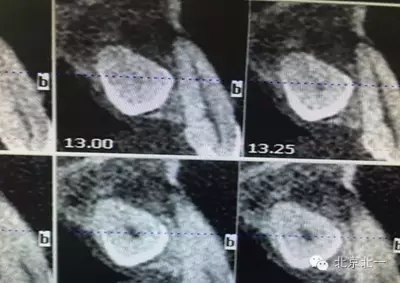

患者種植一月后種植區(qū)不適,偶有疼痛來院拍片發(fā)現(xiàn)23埋伏牙,與種植體相鄰,如圖一、二、三、四所示。